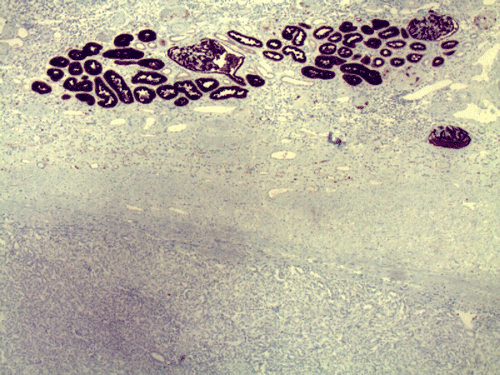

Two major patterns are revealed. In the first pattern, the tumor cells grow in a densely packed tubular pattern with mucinous content (Panel A and B). In some other areas, the tubular pattern is replaced by interlacing fascicles of spindle cells separated by mucinous pools (Panel C and D). In some areas, the spindle cells are solidly packed (Panel E). In both areas, the nuclear are bland in appearance and without significant mitotic acivity. The tumor cells, both in the spindle cell area and tubular areas are strongly positive for cytokerain AE1/AE3, cytokeratin 7, Cam5.2, and epithelial membrane antigen (EMA) respectively (Panel F, G, H and I). The tumor cells are also negative for synaptophysin (Panel J and K) and CD10 (Panel L and M). The positive cells in Panel M are residual non-neoplastic renal tubules. The Ki67 labeling (Panel N) is low (about 1-2%).

These tumors have very characteristic histologic patterns comprised of cuboidal and spindle cells. The cuboidal cells tend to form tubular growth patterns, although trabercular and solid patterns can be identified. Sheets of spindle cells often intersperse between interconnecting tubules, leading to a biphasic appearance. The cells are characterized by eosinophilic cytoplasm, small to medium sized nuclei with little to no atypia, and occasional prominent nucleoli. The surrounding stroma is predominantly myxomatous with a bubbly quality and stains consistently with alcian blue. Studies have shown that a wide majority of MTSCC tumors are positive for epithelial membrane antigen (EMA), AE1/AE3, and cytokeratin 7. In contrast to the classic type of renal cell carcinoma, only about 15% of these tumors are positive for CD10 5. Expression of neuroendocrine markers has also been demonstrated in some tumors 6, 7. Other immunohistochemical markers may be variably positive, including E-cadherin, vimentin, and Ulex Europeus agglutinin-1 (UEA-1). These tumors have a low MIB-1 labeling index. In general, there is not a single marker that could confidently separate this tumor from other renal tumor. The final diagnosis must rest on considerations of morphological and immunohistochemical evidence.